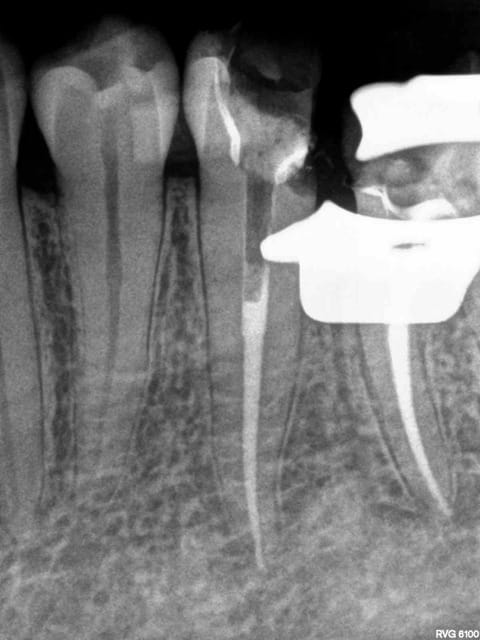

Cas d'école : compos sur 35, 36 2 ans, et endo 35 36 hier.

Surtout pas en faire état tu as raison que ca continue comme ca !

PS : manque une étape, l'endo-peinture canalaire- coiffe, on a perdu des parts de marché sur ce coup là !-)))))